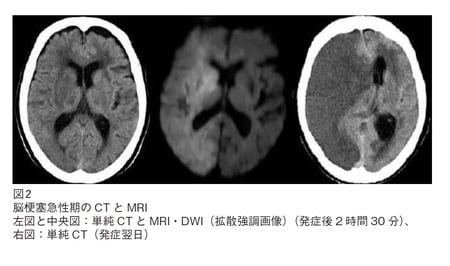

2例目(図表2)は80代後半の女性。突然の意識障害と左片麻痺で発症しました。人工弁置換術を受けた既往歴があります。

左図:発症後2時間の単純CTにて、向かって左側の右半分の脳の腫れのために溝が見えなくなっています。専門的にいえば、

1)右レンズ核の輪郭の不明瞭化

2)右島皮質の不明瞭化(Insular ribbonの消失)

3)右大脳半球全域における皮髄境界の不明瞭化

4)脳溝の消失(tight brain)

を認めます。

中央図:MRIの拡散強調画像DWIでは、右大脳半球のほぼ全域にわたる広範な高信号域を認めます。MRA(未提示)では右内頸動脈閉塞が確認されました。

右図:発症翌日の単純CTでは、右大脳は全般にわたって著明な脳浮腫を伴う広範な低吸収域(脳梗塞)となっています。この患者さんは意識を回復することなく急性期に亡くなられました。

以上、心原性脳塞栓の重症例ばかりの画像をお示ししましたが、他のタイプの脳梗塞も後でたくさん出てきます。また、画像診断も長足の進歩がみられています。CTや通常のMRI撮像法(T1,T2,FLAIR)では、梗塞巣の信号変化がみられない超急性期においても拡散強調画像(diffusion weighted image:DWI)では発症後30分~1時間頃より細胞性浮腫が高信号としてあらわれます(中央図)。